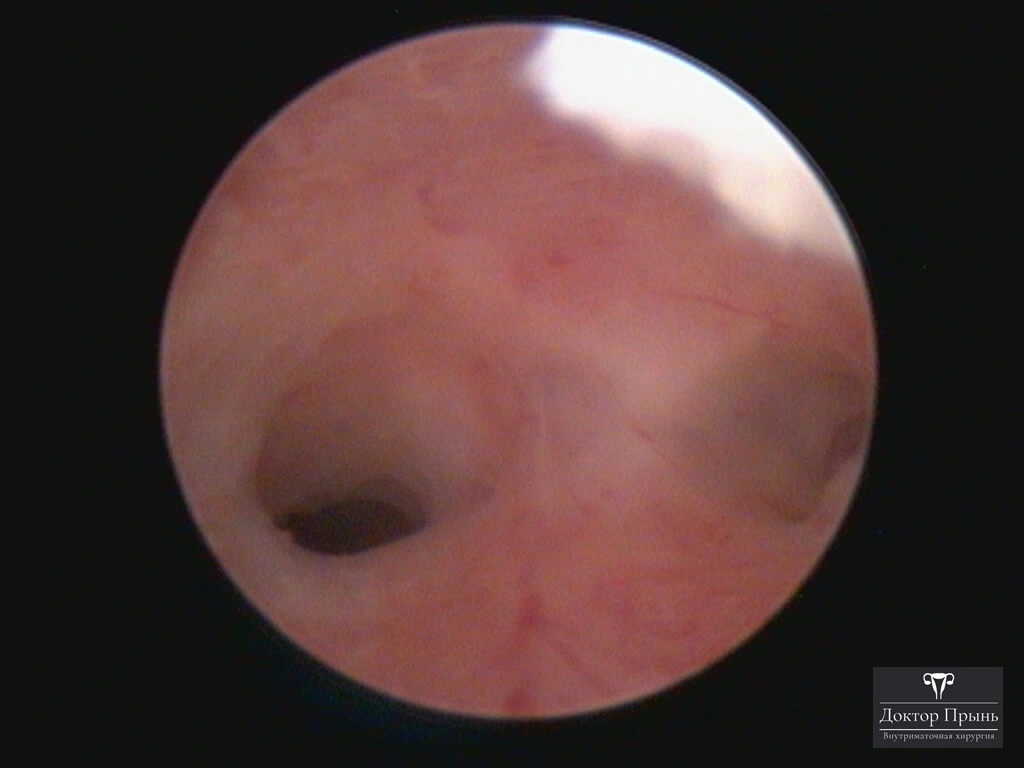

Фотогалерея

Синехии, рассечённые Прынь Д.В.

Гистероскопия позволяет не только увидеть спайки, но и сразу вылечить, т.е. рассечь их. Большинству пациенток подойдёт офисная гистероскопия без наркоза и госпитализации. Среднее время операции 15 минут. Иногда требуется 2-4 операции, чтобы восстановить полость матки.

Крайне важен способ разделения спаек. Если это холодный инструмент, например, ножницы, то вероятность рецидива низкая. Плюс не повреждается нормальный эндометрий. Если рассекают горячей электропетлёй, то, наоборот, риск рецидива высокий и можно обжечь эндометрий.